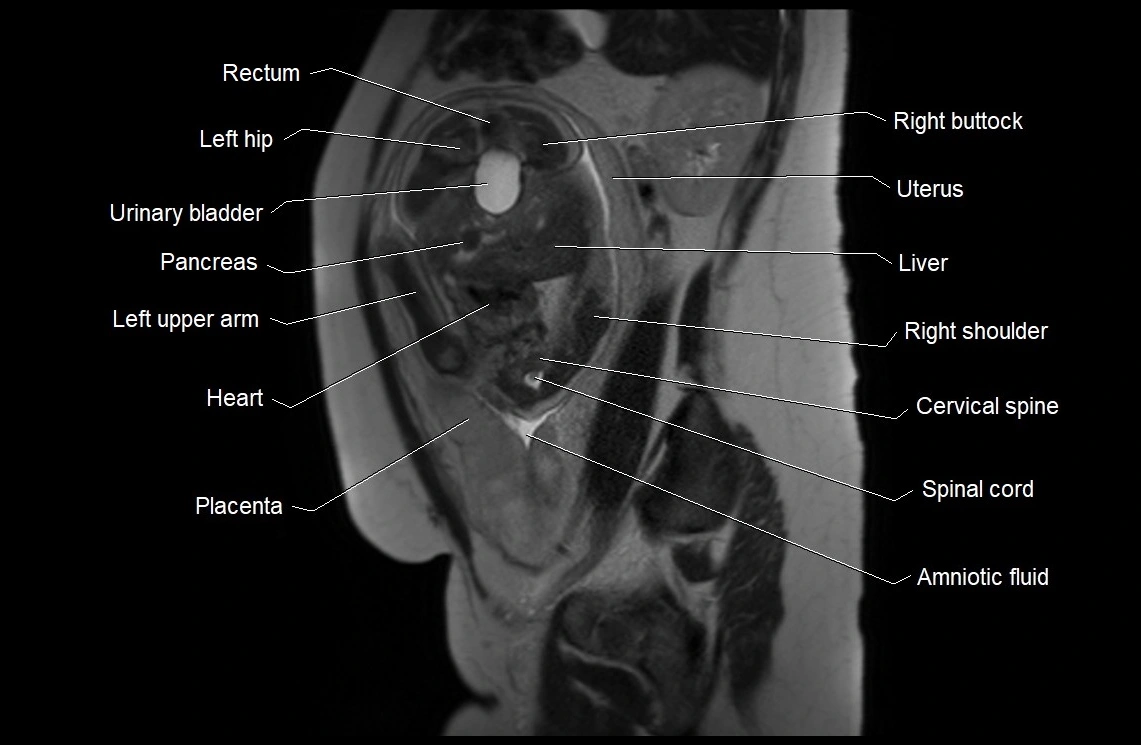

MRI Appearance

T2 HASTE (T2 GRE):

• Amniotic fluid shows very bright hyperintense signal

• Provides natural contrast against fetus and placenta

• Small particles (vernix) may appear as scattered hypointense foci within bright fluid

T1 GRE:

• Amniotic fluid shows low signal intensity (dark)

• Hemorrhage, infection, or proteinaceous content may cause focal or diffuse high signal intensity